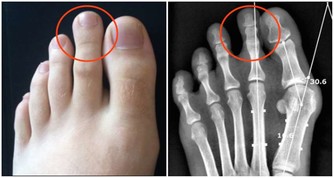

當人們處於壓力之下時,我們的血壓會暫時升高。如果你因為超重或有高血壓家族史而患有高血壓,那麼你的血壓在這種情況下會升高得更多。這是因為你的腎上腺會釋放應激激素,這往往會導致你的心血管系統過度勞累。

如果你長期處在壓力下,每天就會產生應激激素,那麼你的心血管系統會自然進入一種超負荷工作的狀態。這種現象的出現是因為應激激素會增強你的脈搏跳動、呼吸和心跳,時刻準備著“逃跑或者打架”。你的身體會認為你需要戰鬥或跑步,因此你的身體會自然地為其中一種情況做好準備。

經過長時間的壓力,想像一下心臟處在什麼樣的狀態來進行工作。所以,試著散步來緩解充滿壓力的一天。每天要騰出時間來減壓。